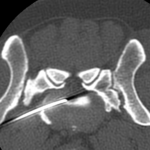

10歳のラブラドールがうまく起立できないとのことで来院されました。神経学的な検査からL7〜S1における腰仙椎間におけるHansen TypeⅡの椎間板ヘルニア、馬尾症候群が疑われました。MRIを撮像したところ、L1~L2にも椎間板ヘルニアが確認されたことから、L7〜S1の椎間板ヘルニアと2ヶ所、同時にPLDDで経皮的に除圧術を行うことになりました。大きな切開を必要としないため翌日退院となります。しばらくは安静にしつつ徐々にリハビリを開始します。